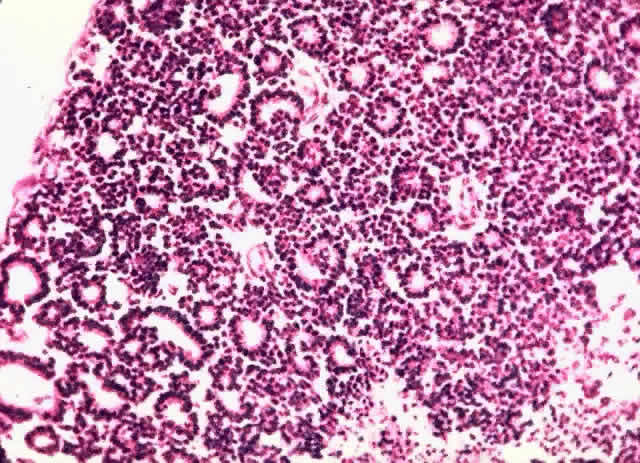

Tumor rosettes were described by Flexner91 in 1881 and Wintersteiner92 in 1897. Multinucleated tumor cells probably represent regression.93 Flexner-Wintersteiner and Homer-Wright rosettes may be seen (Figs. 5 and 6). Flexner-Wintersteiner rosettes are lined with cuboidal cells that have terminal bars at the apical ends, creating a central lumen. These represent an attempt at retinal differentiation set in a field of undifferentiated cells. Homer-Wright rosettes are less characteristic of retinoblastoma. They are associated with medulloblastoma. The cells are arranged around a central tangle of cytoplasmic processes. “Fleurettes” represent a higher degree of maturation. The cells demonstrate evidence of photoreceptor differentiation in small, bouquet-like clusters (Fig. 7). Cell differentiation with fleurettes and FlexnerWintersteiner rosettes may have a better prognosis.52,94 The hereditary variant of retinoblastoma has been shown to be more highly differentiated.95

Fig. 5. Flexner-Wintersteiner rosettes (H & E, × 40).

Fig. 6. Homer-Wright rosette (H & E, × 100).

Fig. 7. Fleurette (H & E, × 125).